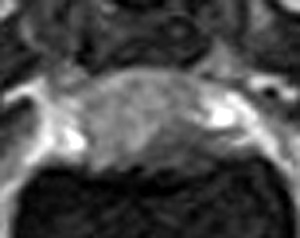

5~6歳以上の去勢手術をしていないオス犬に多い病気ですが、メス犬や去勢した犬に起こることもあります。お尻の筋肉が萎縮した結果、筋肉の隙間から直腸や膀胱が皮膚の下にとびでてしまいます。これにより便が出にくくなったり膀胱炎になったりします。手術をすることで機能回復および今後の致死的な状況を回避することができます。当院では去勢手術→結腸固定→前立腺固定→骨盤隔膜構成筋の縫縮→内閉鎖筋フラップ→浅臀筋フラップの順で通常腹側・臀部左右両側同時に行います。また老化以外に、筋肉が萎縮する原因があったり、腹圧がかかる原因があったりする場合も多いので、再発防止のためそれらの診断・治療も重要です。今回のワンちゃんも無事手術も終わり元気に退院しました。よかったね。